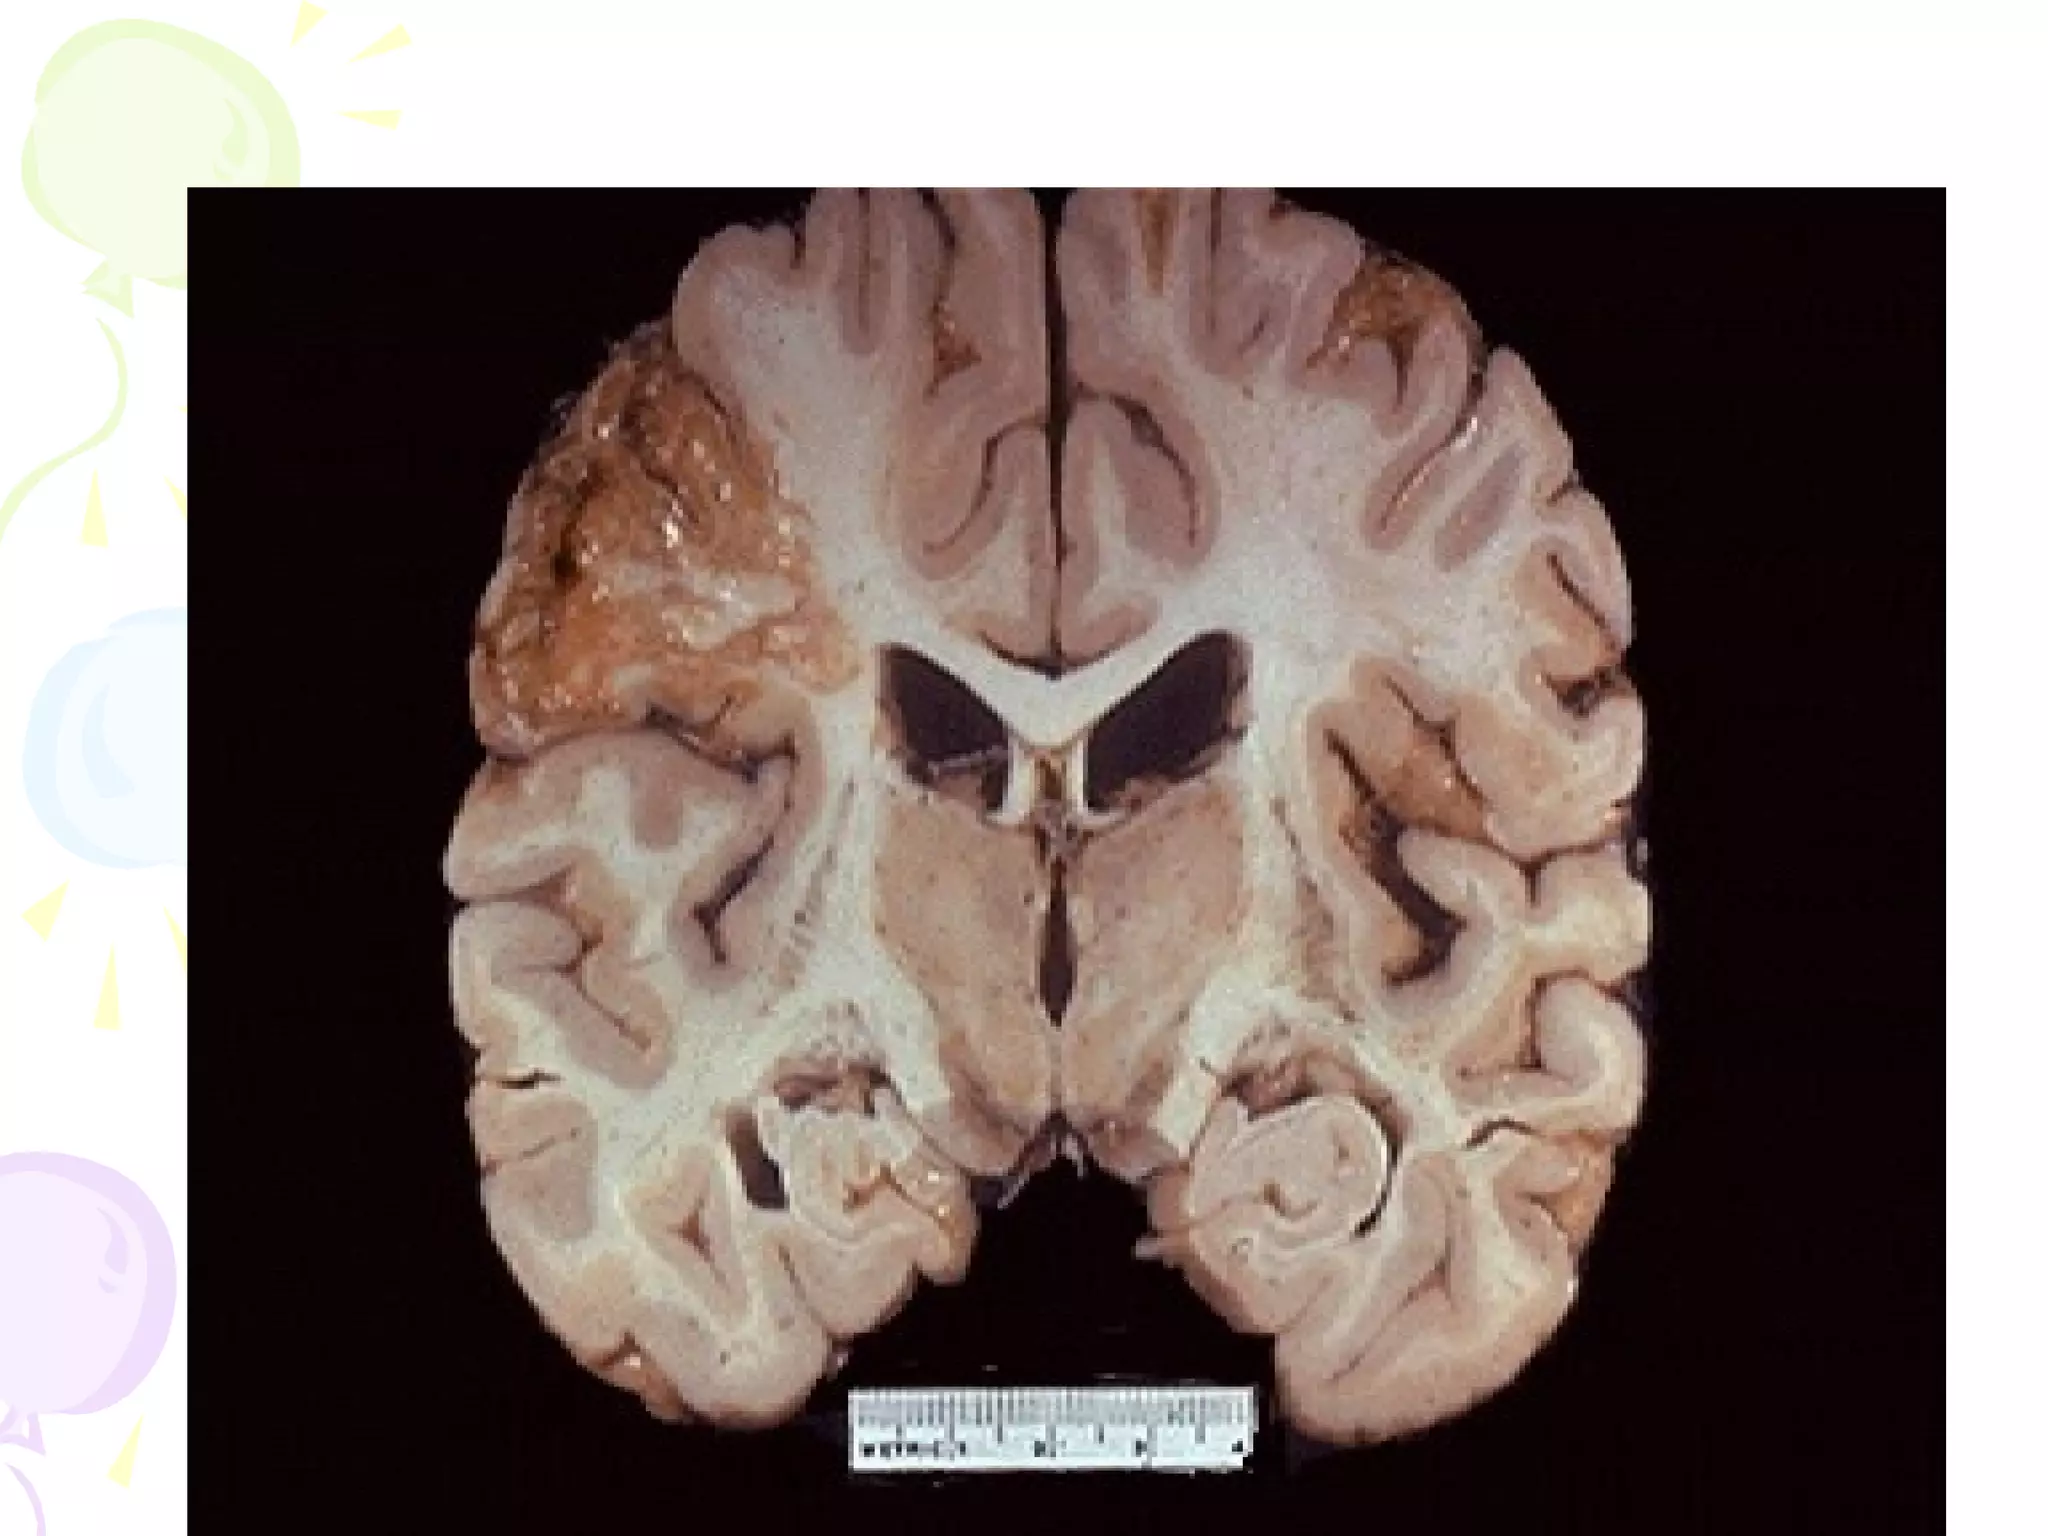

• Liquefactive Necrosis

- focal bacterial (or fungal) infections

– accumulation of inflammatory

cells

- hypoxic death of cells within CNS

LIQUEFACTIVE NECROSIS

• (* "colliquative necrosis" in Europe): When

the cells die, they are rapidly destroyed by

lysosomal enzymes, either their own or

those from neutrophilic leukocytes

• The tissue becomes liquid viscous mass

• Material is creamy yellow in color

• Seen in ischemia of brain, abscess

Normal brain   Liquefactive necrosis